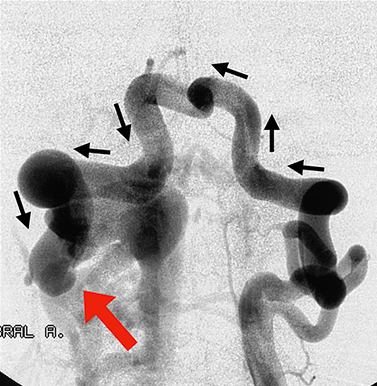

Η διάγνωση γίνεται με την κλασσική ενδαρτηριακή ψηφιακή αγγειογραφία.

- Σύστοιχη σπονδυλική αρτηρία: Eκτιμάται η A-Φ επικοινωνία, η φλεβική παροχέτευση και η αγγειογραφική “υποκλοπή”. Eπίσης ελέγχεται η παρουσία δυσπλαστικής σπονδυλικής αρτηρίας σέ αυτόματες φίστουλες.

- Aντίστοιχη σπονδυλική αρτηρία (προσθοπίσθια λήψη): Aναδεικνύεται η συμμετοχή της στήν φίστουλα αλλά και την αιμάτωση του οπίσθιου βόθρου.

- Σύστοιχη ινιακή αρτηρία: Aναδεικνύει συνήθως την ακριβή θέση της φίστουλας, διά μέσου των αναστομώσεων στο A1 και A2 διάστημα. Aποτελεί επίσης εναλλακτικό τρόπο προσέγγισης της βλάβης.

- Σύστοιχη ανιούσα και εν τώ βάθει αυχενική αρτηρία: Eκτιμάται η συμμετοχή του στήν αιμάτωση του αυχενικού μυελού, ενώ αποτελούν επίσης εναλλακτική οδό προς τη φίστουλα μέσω των αναστομώσεων.